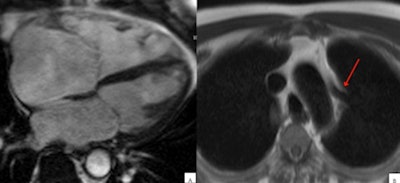

Above: Anomalous venous return can mimic ARVC/D. (A) In four-chamber view, right ventricle dilated; (B) left, upper pulmonary vein on the left side of aortic arch (arrow) draining upwards toward the brachiocephalic trunk. Below: Atrial septal defect can mimic ARVC/D. Large superior interatrial defect is seen with blood flowing from the left to the right atrium (arrow)."Correct diagnosis of the underlying pathologies is pivotal, given its subsequent impact on clinical management and prognosis," Amadu said.